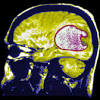

How glioblastoma is treated (CNN) - Glioblastoma, an aggressive type of cancer that can occur in the brain or spinal cord, quickly became a household term after Sen. John McCain was diagnosed with the brain tumor in July 2017.

What is glioblastoma? On Friday, his family said in a statement that McCain had made the decision to discontinue medical treatment. Unlike other brain tumors that start in the body and spread to the brain, glioblastoma starts in the brain or spinal cord.

How glioblastoma is treated (CNN) Glioblastoma, an aggressive type of cancer that can occur in the brain or spinal cord, quickly became a household term after Sen. John McCain was diagnosed with the brain tumor in July 2017.